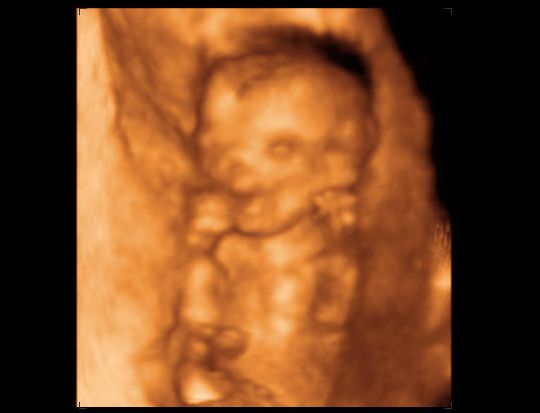

Régen voltam erre, bocsánat, írok magunkról egy kis összefoglalót. Ugye a 12. heti kombináltról asszem írtam, hogy rendben volt, bár a Down-kór kockázat 1:1042, de azt mondták az én koromban (35) ez nem olyan rossz, pláne, hogy az UH-n mindent rendben találtak - Hajdu Krisztina szerint tökéletes baba! 8) A 15. héten elkezdtem keményedni, de a doki mindent rendben talált, és mivel furdalt minket a kiváncsiság, elmentünk 4D-re. Gyönyörű képek születtek, többek között ez a vigyori:

Kép